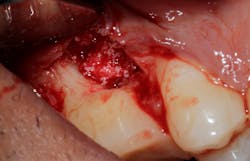

Saving compromised multirooted teeth with root amputation can often be successful, but the technique is sensitive and complex. Proper case selection is essential, and considerations include the following:

There is sufficient bone support around the remaining roots (at least 50% or more is needed) along with sufficient coronal tooth structure (figure 3).How does root amputation compare with other surgical procedures?

The prognosis is good for molar teeth treated with root amputation, provided case selection and treatment are performed properly. Fugazzottoreported 15-year cumulative success rates comparing molar root resection to molar implant placement, with survival rates of 96.8% for root-resected molars and 97.0% for molar implants.10 This study was done in private practice with proper oversight and case selection.Conclusion

Root amputation remains a viable treatment to save maxillary molars and can have long-term success rates equal to dental implant therapy (figures 9 and 10).Editor’s note: This article originally appeared in Perio-Implant Advisory, a chairside resource for dentists and hygienists that focuses on periodontal- and implant-related issues. Read more articles and subscribe to the newsletter.